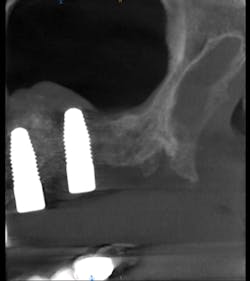

I prescribed a CBCT scan to evaluate site No. 14 prior to implant placement and to evaluate tooth No. 15. After capturing a CBCT scan on the CS 9300 (with a 5 cm x 5 cm field of view and a resolution of 90 μm), the image clearly showed a palatal root fracture on tooth No. 15 across from the cross-sectional and axial scan views (figs. 1, 2). Thanks to the enhanced diagnostic quality of the images, we decided to extract the tooth.

Figure 1: